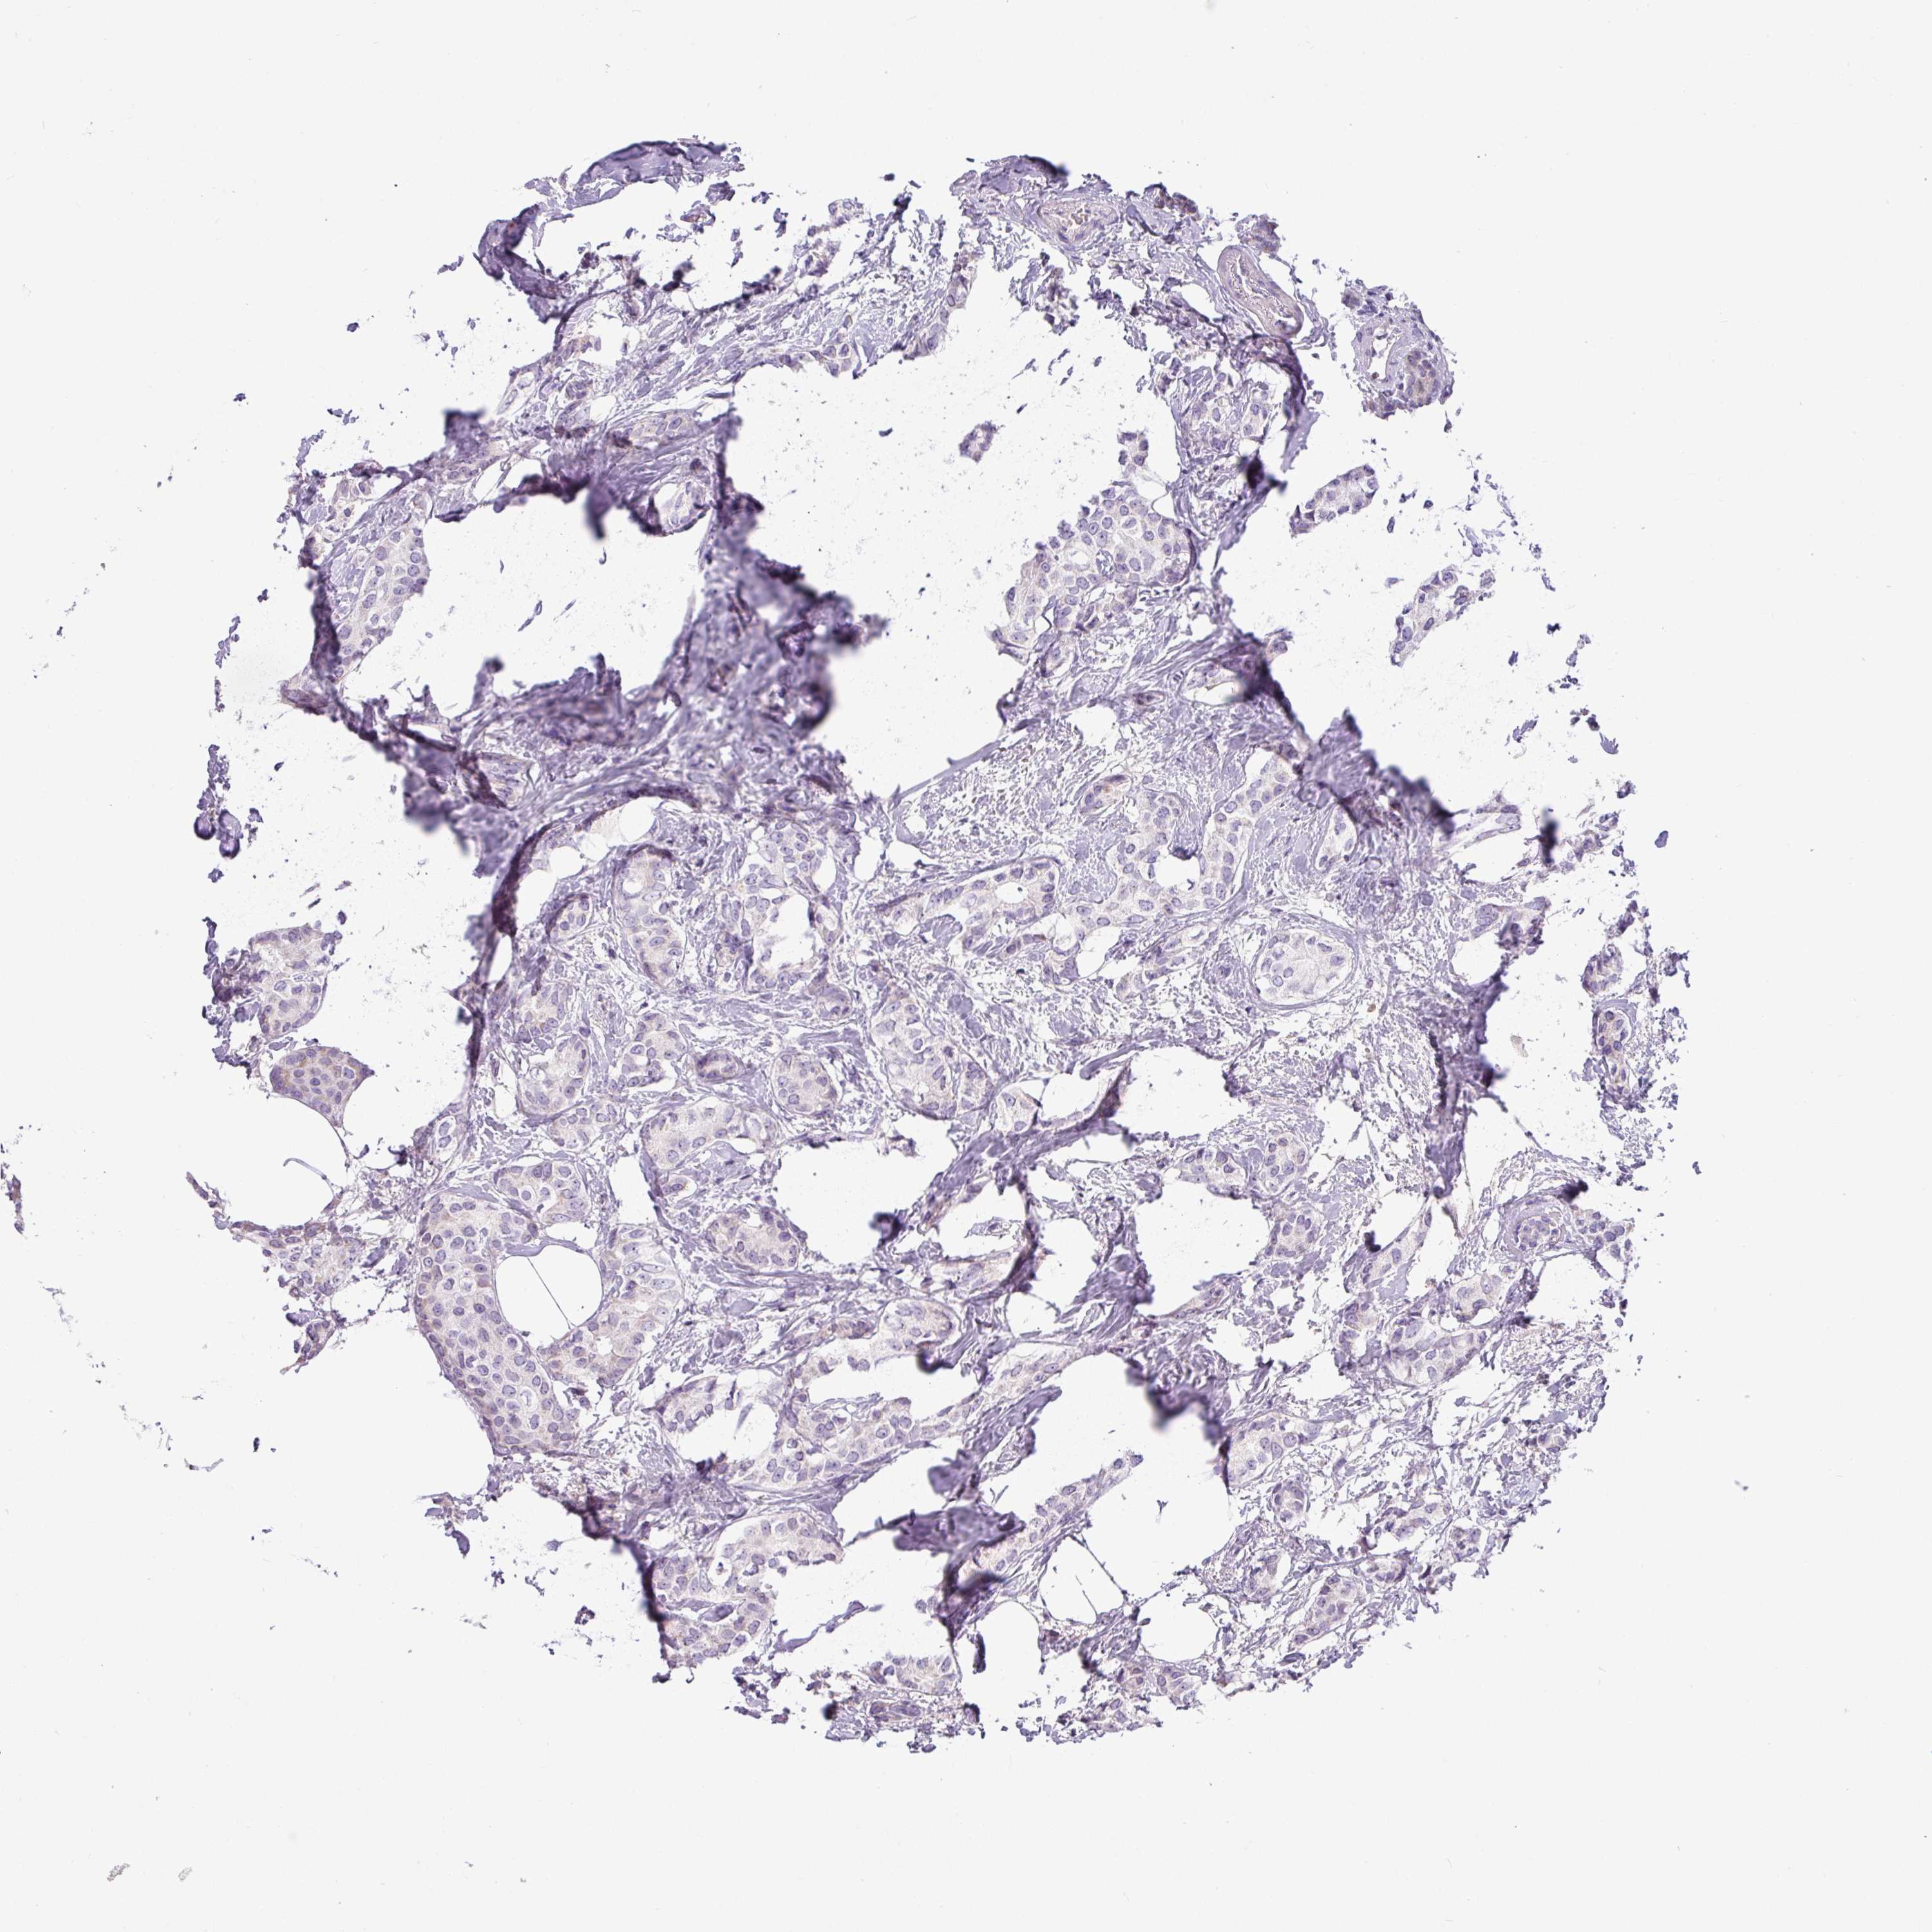

CANCER BREAST CANCER Show tissue menu

Breast cancer

Human cancer

SH2D3C is not prognostic in Breast Invasive Carcinoma (TCGA)